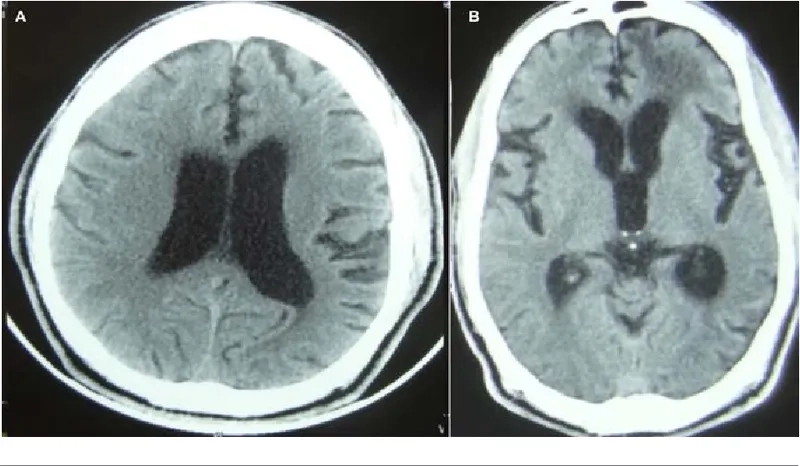

Comparing NPH to other forms of dementia